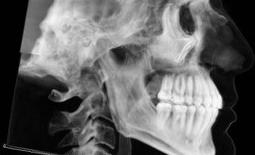

Clinical evaluation showed a mild Class III skeletal pattern with a constricted maxilla, mildly dolichofacial and straight

profile (Figure 1). Full adult dentition was present with all third molars extracted. Maxillary and mandibular incisors were normoclined. The maxillary midline coincided with the facial midline, and the mandibular midline was 2 mm to the right of the facial midline. There was a 2 mm to 5 mm lateral open bite on the right side from the second molar to the lateral incisor, and the maxillary occlusal plane was canted to the left of the interpupillary line. A lateral tongue thrust into the open bite was noted on swallow.

The right side was in posterior crossbite and there was an edge-to-edge anterior bite with wear on the maxillary central incisors. Mild gingival recession was noted, but soft tissue was generally within normal limits. CBCT analysis found no radiographic evidence of osteoarthritis in the TMJ joints, nor osseous or apical pathology involving the maxillary or mandibular teeth. His airway was not constricted. Initial report from the myofunctional therapist indicated that the patient never developed a mature swallow sequence and had a bilateral posterior tongue thrust.

Figure 1. Initial records.